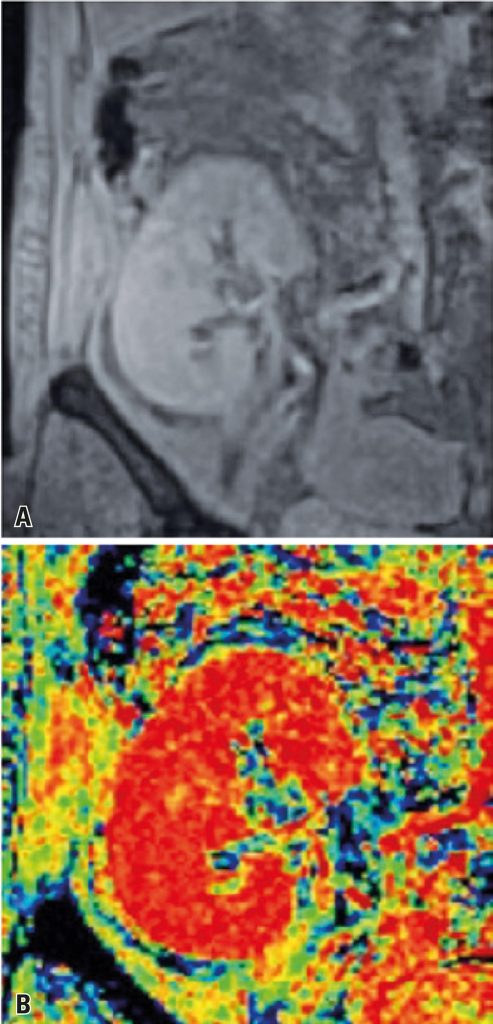

Evaluation of the blood-oxygen-level-dependent (BOLD) sequence with 3 Tesla device in renal transplant patients in the assessment of early allograft disfunction, correlated with biopsy

To evaluate the ability of blood-oxygen-level-dependent (BOLD) magnetic resonance imaging at 3 Tesla to measure tissue oxygen bioavailability based on R2* values, and to differentiate between acute tubular necrosis and acute rejection compared to renal biopsy (gold standard).

A prospective, single-center study, with patients submitted to renal transplantation between 2013 and 2014, who developed graft dysfunction less than 4 weeks after transplantation. All patients were submitted to abdominal magnetic resonance imaging at 3 Tesla using the same protocol, followed by two BOLD sequences and kidney biopsy.

Twelve male (68.75%) and three female (31.25%) patients were included. A total of 19 percutaneous renal biopsies were performed (four patients required a second biopsy due to changes in clinical findings). Pathological findings revealed ten cases of acute tubular necrosis, four cases of acute rejection, and five cases with other (miscellaneous) diagnoses. Comparison between the four groups of interest failed to reveal significant differences (p=0.177) in cortical R2* values, whereas medullary R2* values differed significantly (p=0.033), with lower values in the miscellaneous diagnoses and the acute tubular necrosis group.

BOLD magnetic resonance imaging at 3 Tesla is a feasible technique that uses indirect tissue oxygen level measurements to differentiate between acute rejection and acute tubular necrosis in renal grafts.